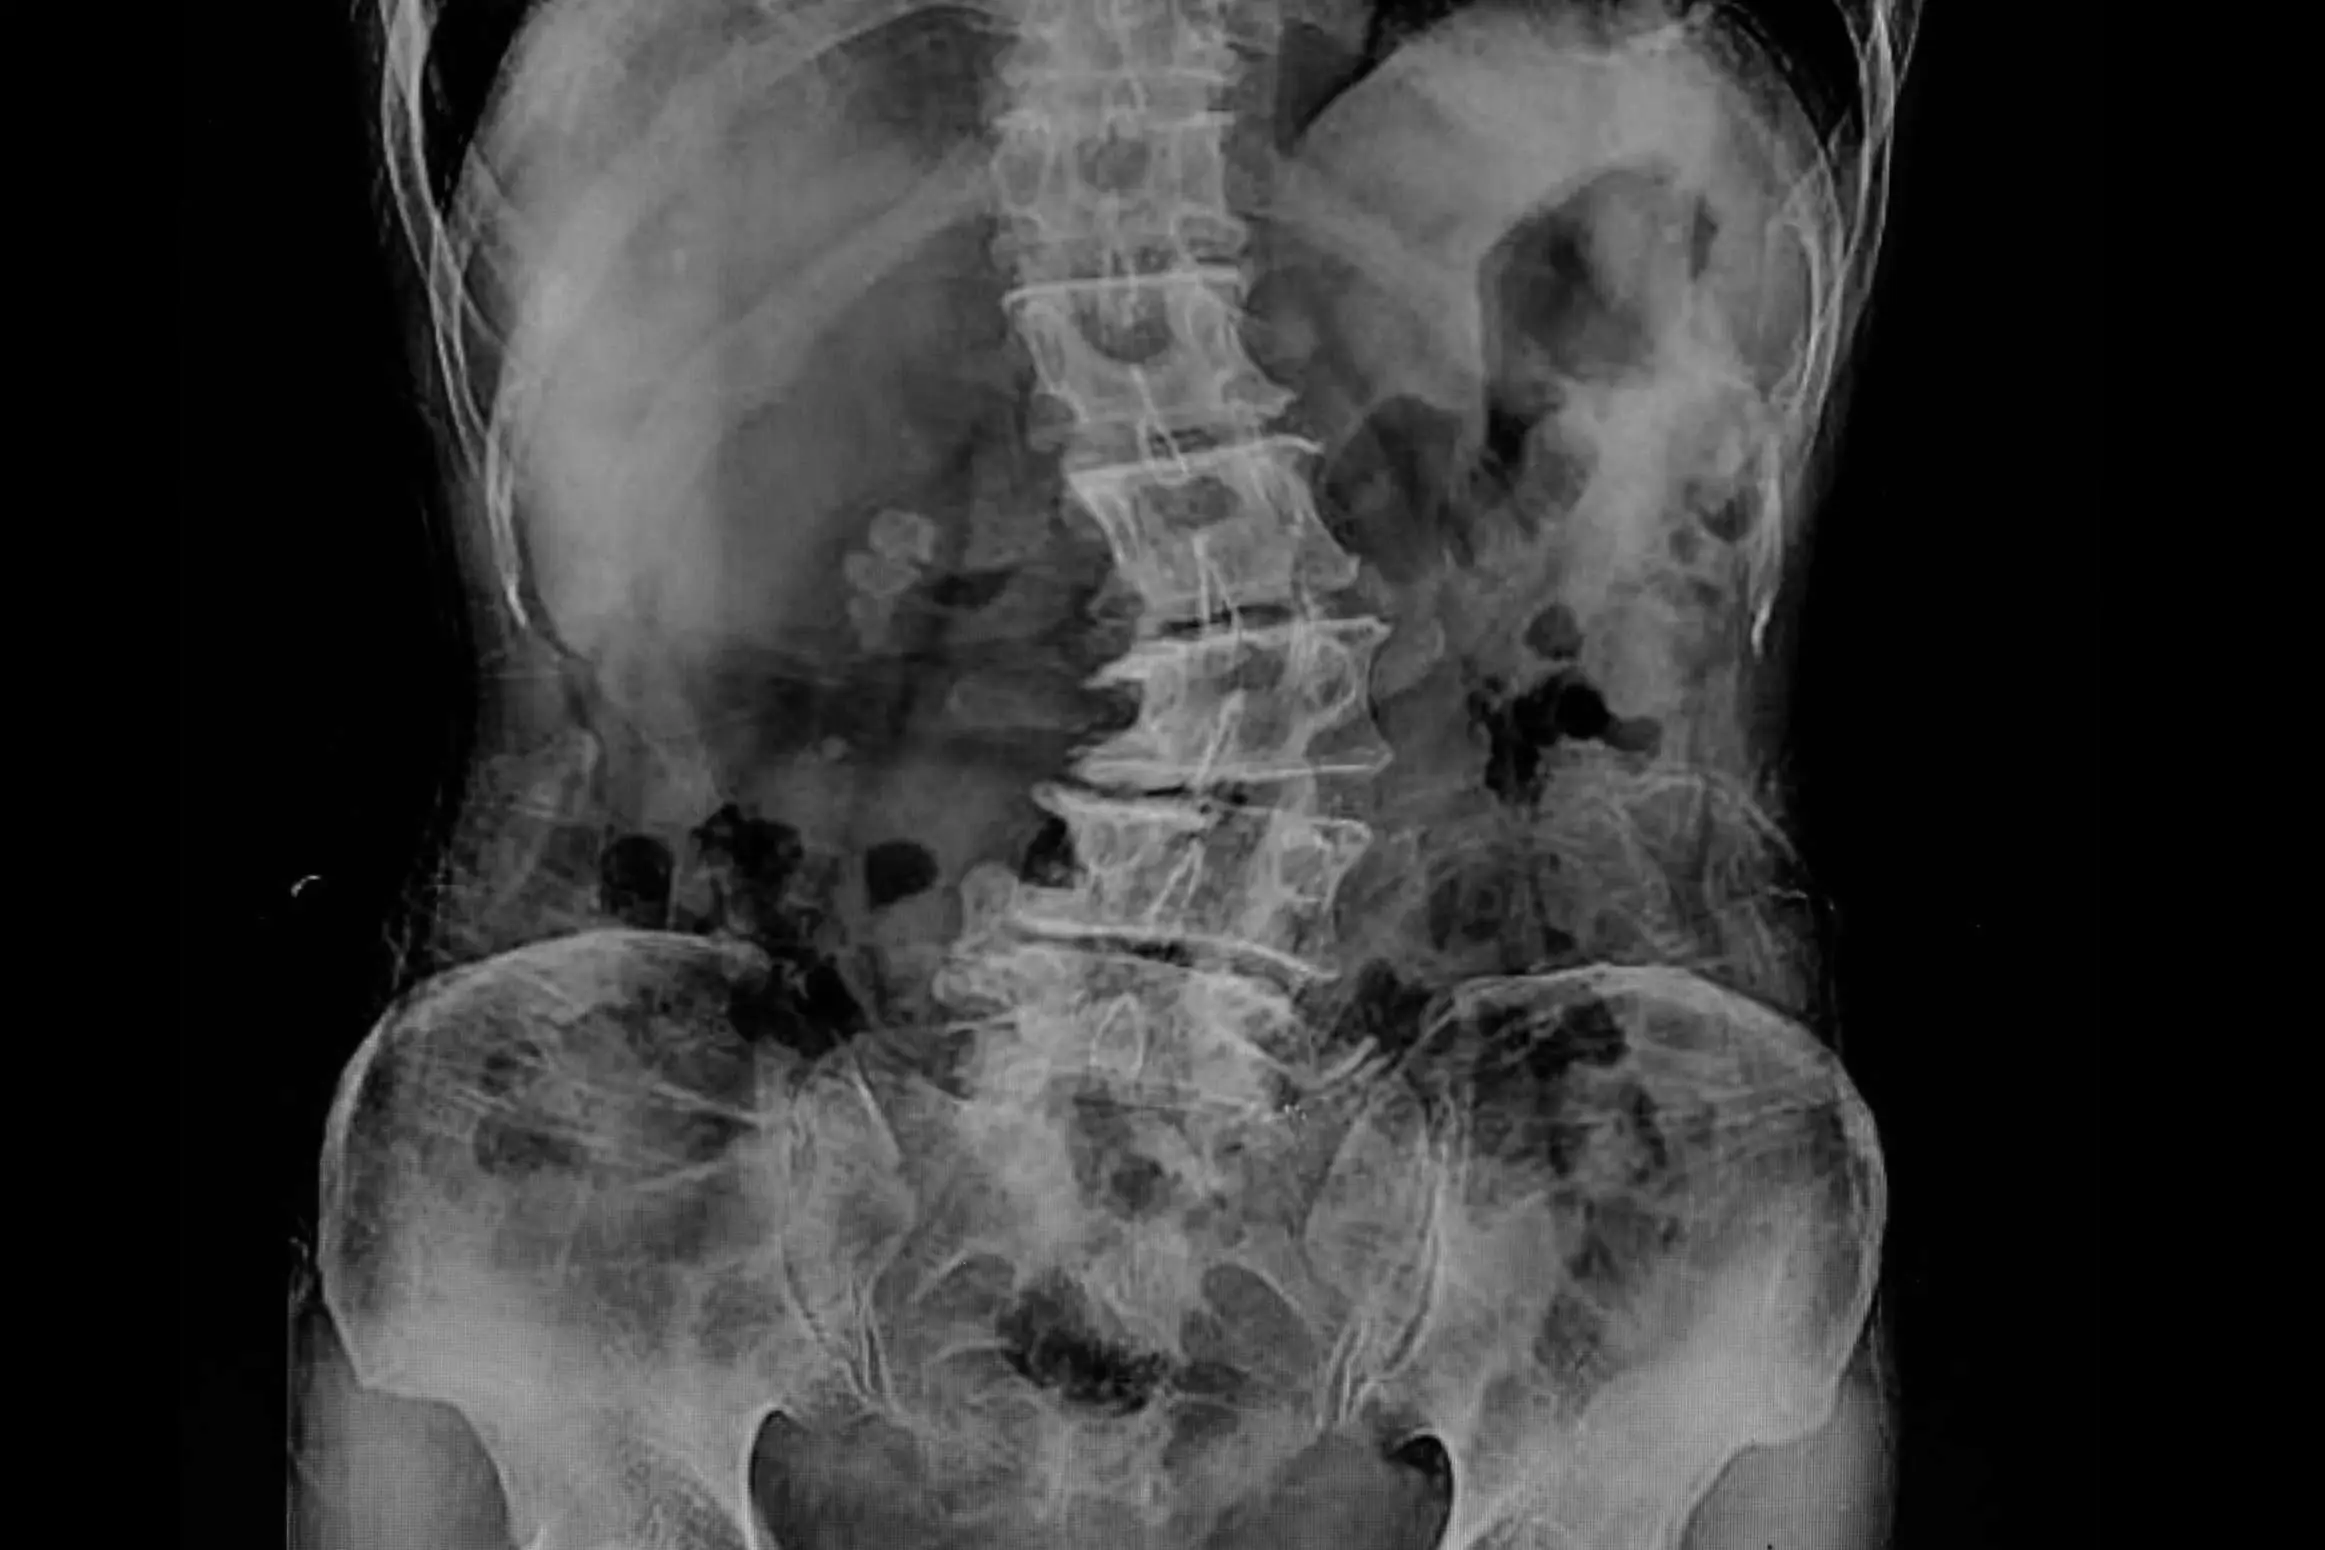

De acuerdo con los expertos de Biziondo, la escoliosis lumbar es una deformidad de la columna que se caracteriza por una curvatura lateral de la misma, provocando que adopte una forma de S o de C. Esta condición puede generarse como resultado de factores genéticos, enfermedades neuromusculares o lesiones en la parte inferior de la columna vertebral.

Para diagnosticar la escoliosis lumbar, los profesionales de la unidad médica Biziondo pueden llevar a cabo un examen físico, una radiografía de la columna vertebral o una resonancia magnética. En ese sentido, lo ideal es obtener un diagnóstico temprano mediante un examen médico, con la finalidad de prevenir la aparición de complicaciones a largo plazo.